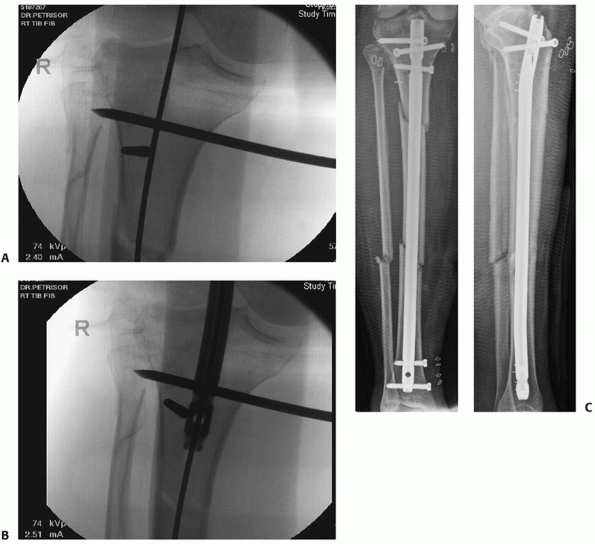

nailing, of proximal tibial fractures has been associated with some

difficulties.24,210,273

This has been due to many factors such as the proximity of the fracture

line to the joint, maintaining and obtaining a reduction while nailing,

and difficulties with the passage of an intramedullary nail through the

proximal fracture

fragment.

evidence: 4).283 Krettek et al.156,157

have described the technique of using blocking screws in 23 proximal

and distal fractures. They found a mean loss of reduction of 0.5

degrees in the frontal plane and 0.4 degrees in the sagittal plane.156,157

Blocking screws are placed so as to effectively reduce the size of the

tibial canal either proximally or distally and thereby guide both the

guide wire and the nail into an acceptable position. They can be placed

in any plane but are usually placed in either the sagittal or coronal

planes. Techniques for preventing or minimizing malalignment when using

an intramedullary nail for extra-articular proximal diaphyseal

fractures will be discussed in the authors’ preferred method of

treatment section.